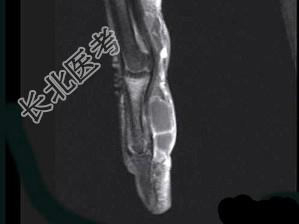

- 单项选择题女,77岁, 发现右手部肿块2周,结合图像, 最可能的诊断是 ( )

A、肌内脓肿

B、多发性腱鞘囊肿

C、骨囊肿

D、血管瘤

E、以上都不是